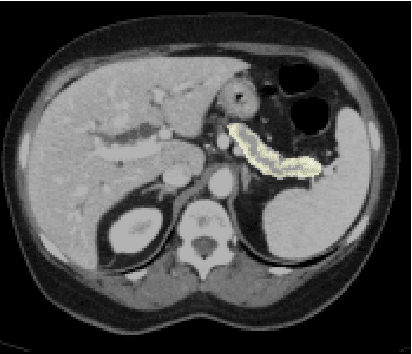

Abstract:For artificial intelligence-based image analysis methods to reach clinical applicability, the development of high-performance algorithms is crucial. For example, existent segmentation algorithms based on natural images are neither efficient in their parameter use nor optimized for medical imaging. Here we present MoNet, a highly optimized neural-network-based pancreatic segmentation algorithm focused on achieving high performance by efficient multi-scale image feature utilization.